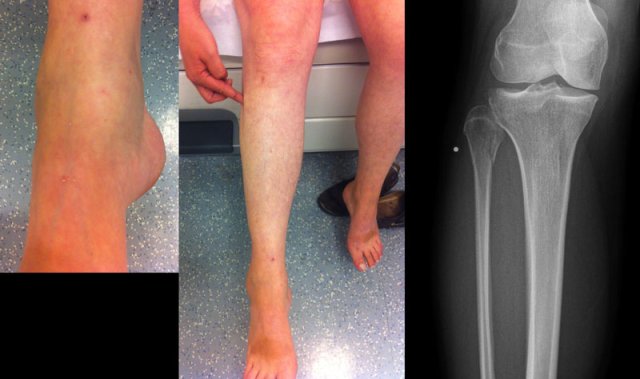

This patient had a twisted ankle and the only abnormality is seen on the lateral view.

This was thought to be an avulsion of the posterior malleolus.

Knowing that this can be the only clue to a high Weber C, additional radiographs were taken.

Continue with the images of the lower leg.

A subtle high fibula fracture is seen (arrow).

Final diagnosis is a Weber C fracture or according to Lauge Hansen: Pronation Exorotation injury stage 4.